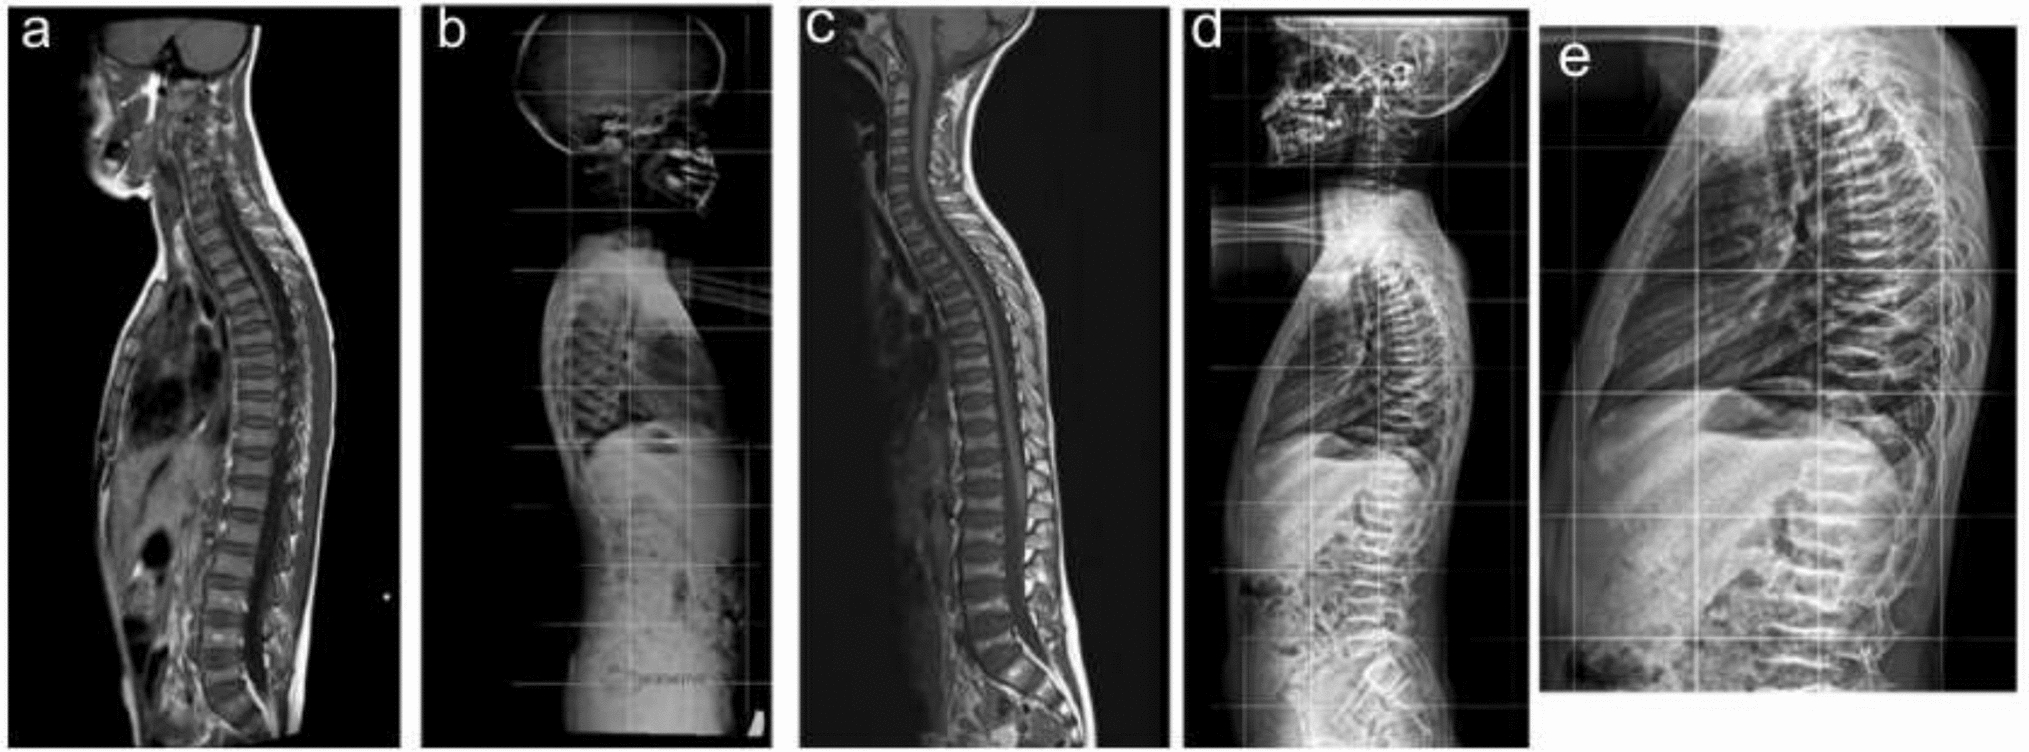

Base of Skull & Spinal Canal Narrowing in an Adolescent with Autosomal Recessive Hypophosphatemic Rickets Type 2

Autosomal recessive hypophosphatemic rickets type 2 (ARHR2) is an uncommon hereditary form of rickets characterised by chr...